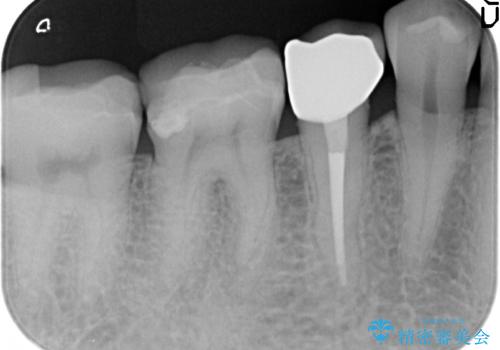

検査の結果右下5番目の歯の神経が死んでいたため、根管治療を行った後、オールセラミッククラウンによる補綴を行いました。

今回用いたオールセラミッククラウンはジルコニアフレームという白い素材の上にセラミックを盛っているため、審美性が非常に高いのが特徴です。

また、ジルコニアは人工ダイヤモンドの材料にも使われているほど高い強度を持っており、そのためオールセラミッククラウンは審美性だけでなく、奥歯やブリッジの補綴も可能とするクラウンです。